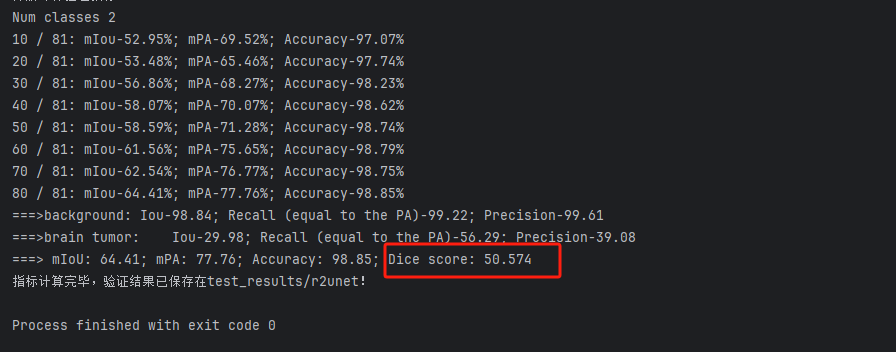

以我们的数据为例,下面是改进模型1得到的结果。